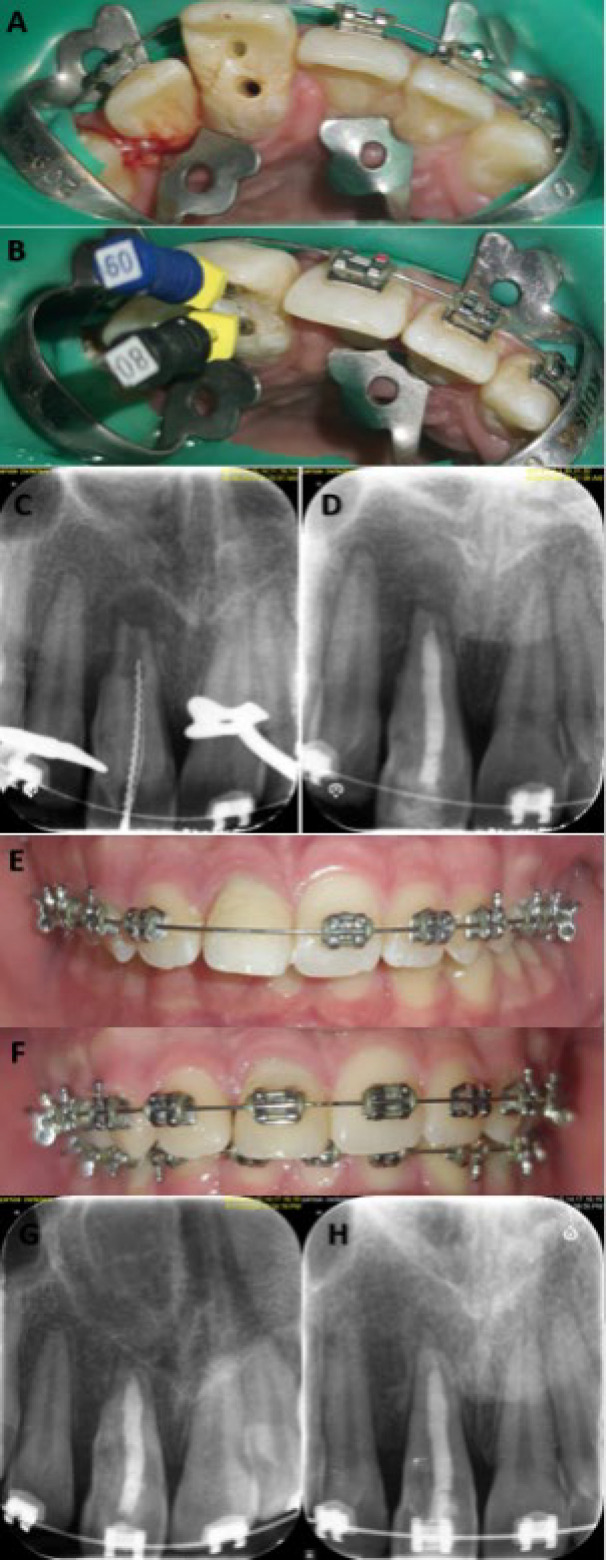

内凹牙是由于牙釉质和牙本质向牙髓内折叠而引起的发育异常。Oehlers的IIIa型牙槽内陷由于其复杂的解剖结构和经常与未成熟牙齿相关而面临重大挑战。本病例报告概述了一个非重要的未成熟上颌中切牙IIIa型牙槽内陷的非手术治疗,表现为慢性根尖脓肿和相关的上切牙创伤史。治疗包括彻底的化学机械清创,然后使用富钙混合水泥进行生物封闭。定期随访发现根尖周围病变完全消退。这个病例强调了精确诊断、个体化治疗计划和应用先进生物材料在解决复杂凹牙表现的重要性。成功的结果强调了非手术技术在保留未成熟牙齿的同时恢复功能和美观的有效性。

Dens invaginatus is a developmental anomaly resulting from the infolding of enamel and dentin into the dental pulp. Oehlers' Type IIIa dens invaginatus poses significant challenges due to its intricate anatomy and frequent association with immature teeth. This case report outlines the nonsurgical management of a nonvital immature maxillary central incisor with Type IIIa dens invaginatus, presenting with a chronic apical abscess and a history of trauma to the associated primary incisor. Treatment involved thorough chemomechanical debridement followed by bio-obturation using calcium-enriched mixture cement. Regular follow-ups revealed complete resolution of the periapical lesion. This case underscores the importance of precise diagnosis, individualized treatment planning, and the application of advanced biomaterials in addressing complex presentations of dens invaginatus. The successful outcome emphasizes the efficacy of nonsurgical techniques in preserving immature teeth while restoring function and aesthetics.